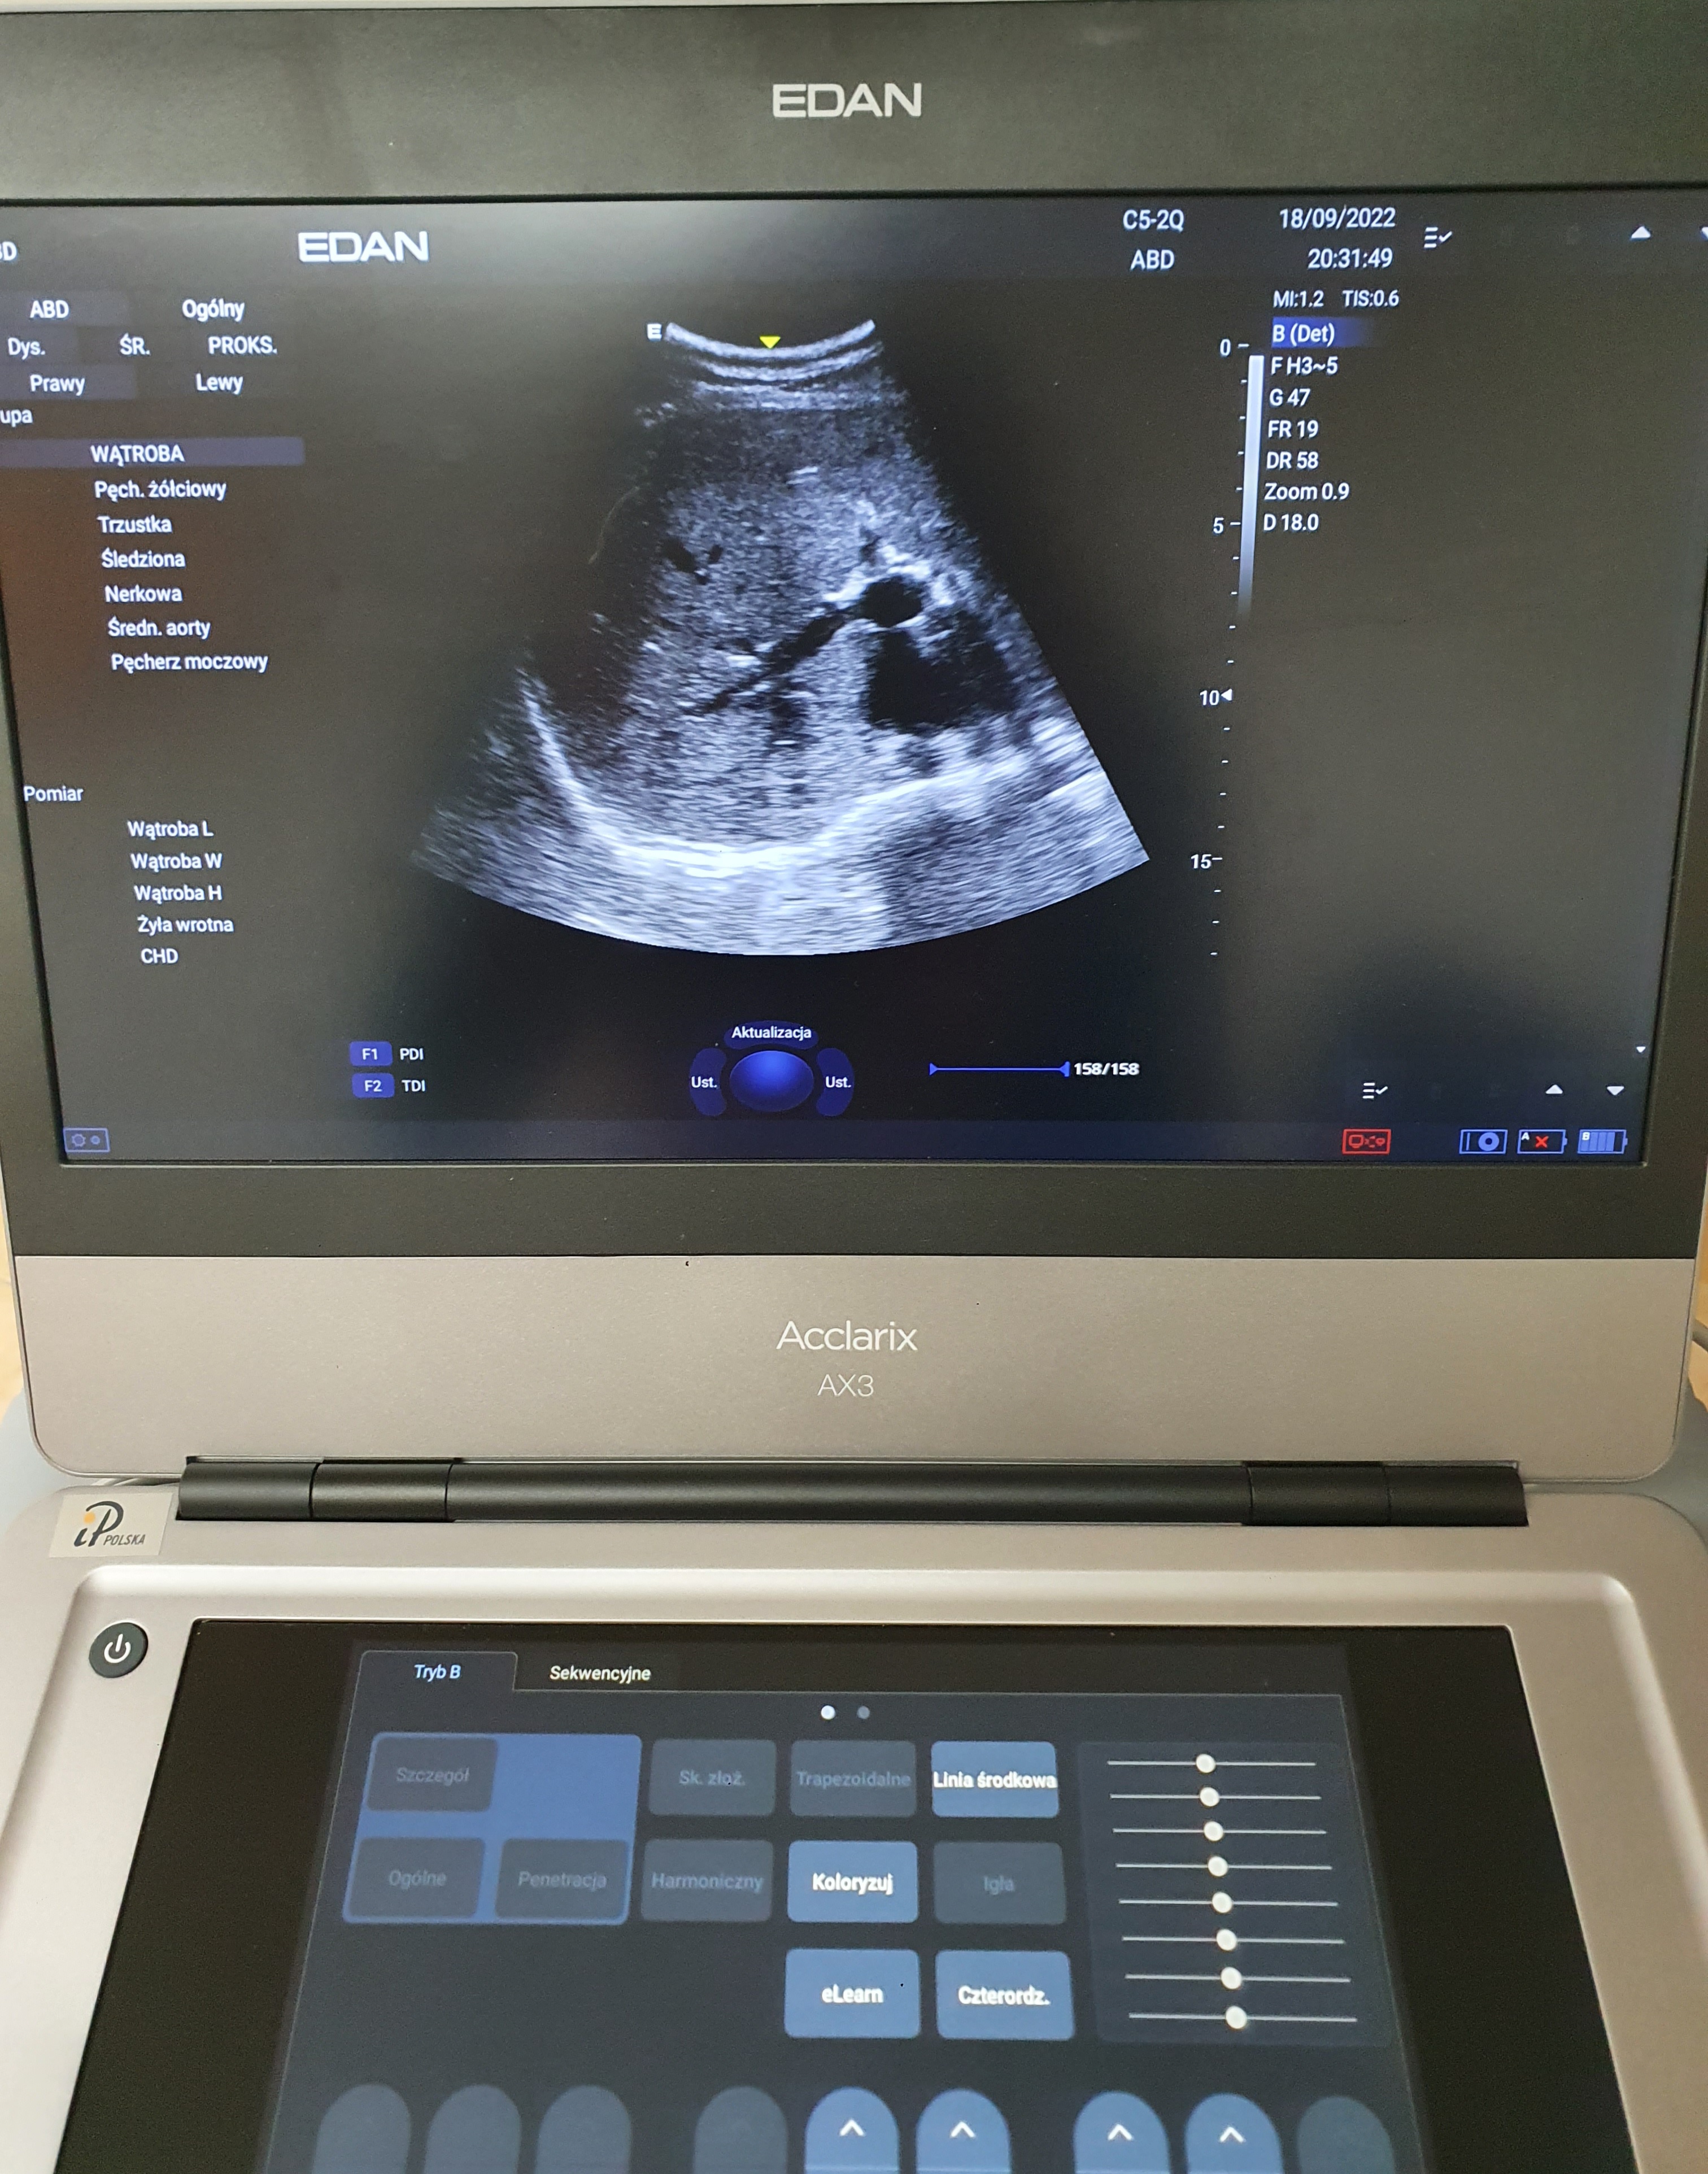

Aparat USG Edan Acclarix AX3, 2 głowice (kardio, convex), stolik

Sprzedam aparat USG Edan Acclarix AX3- kompaktowy, przenośny, wytrzymały aparat USG pracujący na cyfrowej platformie medycznej Android, wyposażony w ekran dotykowy, 2 głowice- kardiologiczna i convex, kabel pacjenta do EKG, dedykowany stolik. Stan idealny, zestaw zakupiony nowy w styczniu 2022 roku za 67 000 zł, jest na gwarancji do stycznia 2024. Używany był sporadycznie. Sprzedaję ponieważ zmieniam profil działalności gabinetu. Acclarix AX3 spełnia wymagania NFZ (ultrasonograf typu I, II i III) oraz Polskiego Towarzystwa Ultrasonograficznego. Wystawiam fakturę